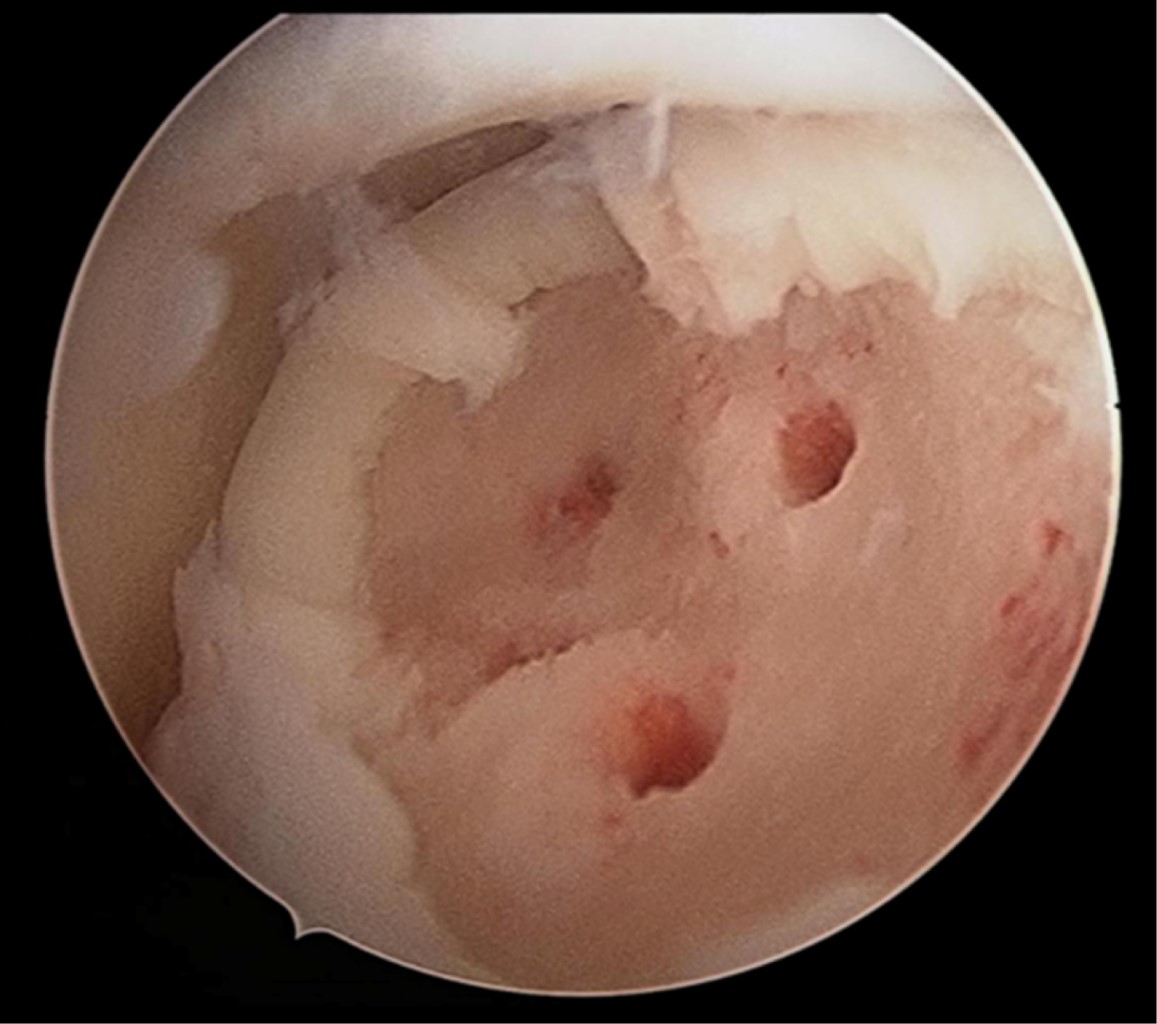

Figura 1